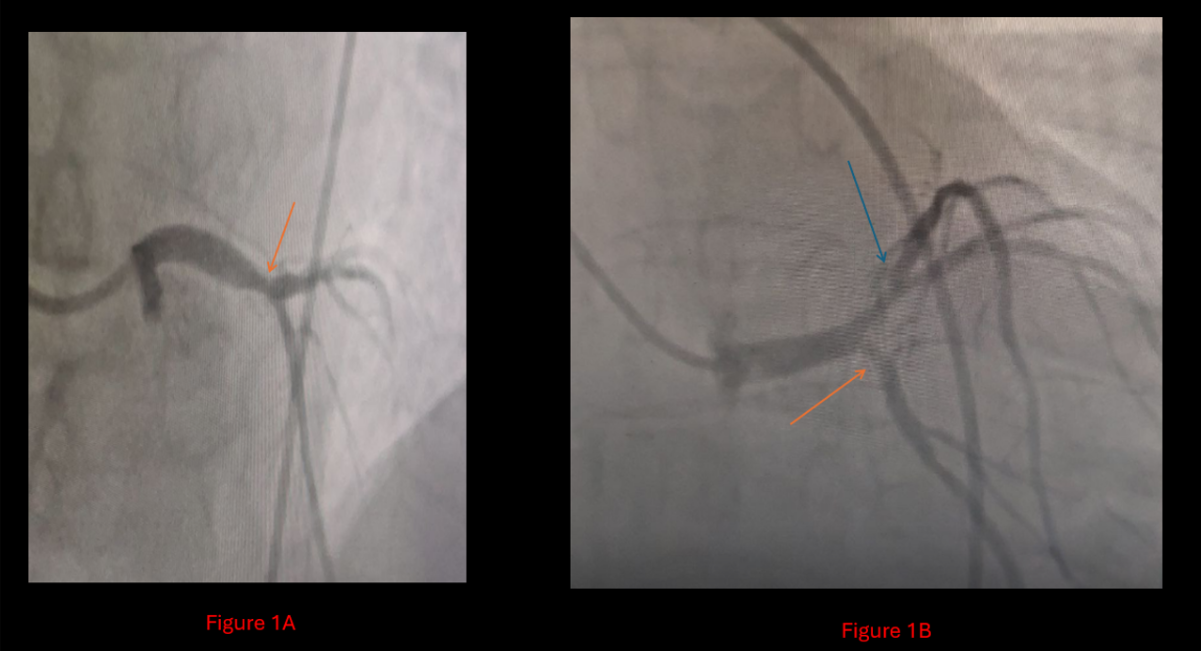

The patient had been evaluated at multiple tertiary centers, all of which declined surgical intervention due to his high-risk status and multiple comorbidities. At presentation to Al-Bashir Hospital, he experienced ongoing chest pain consistent with unstable angina. Coronary angiography revealed: 60% calcified stenosis in the Left Main (LM) artery, 70% calcified stenosis at the ostium of the Circumflex (Cx), and In-Stent Restenosis (ISR) in the previously stented LAD segment with significant calcification adjacent to the under expanded stent (Figure 1).

Figure 1A: Diagnostic catheterization showing 60% left main artery stenosis, and for

Figure 1B: A 70% ostial circumflex stenosis is indicated by the orange arrow, in addition to In-Stent Restenosis (ISR) in the left anterior descending artery with significant calcification between the collapsed stent and the arterial wall is indicated by the blue arrow